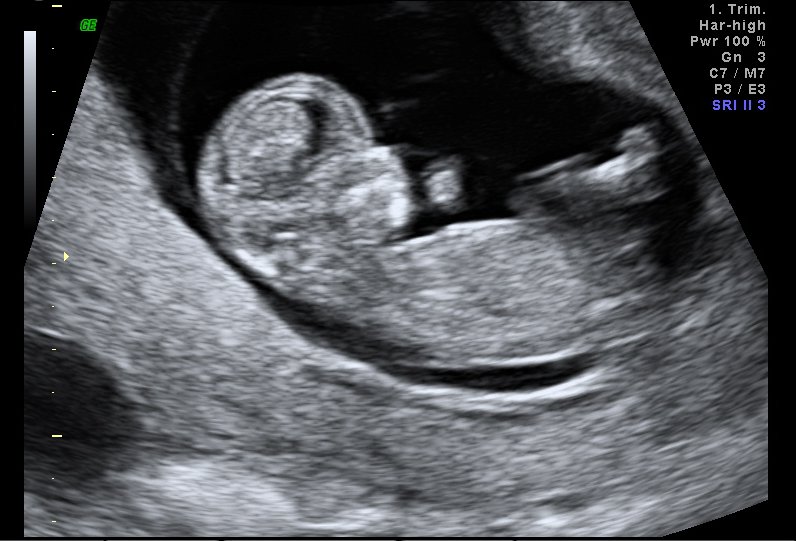

11.5 weeks, everything looks good so far. [thumbsup]

[thumbsup]  awwww! I remember when mine looked like that ;D